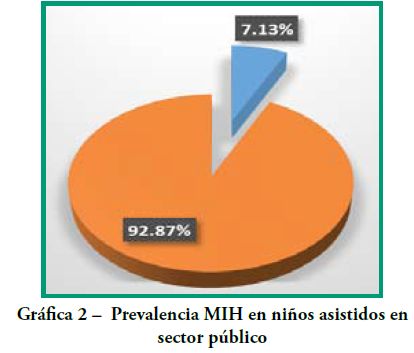

Los resultados intragrupo se representan en las Gráficas 1-6.

Grupo 2 Secor Público:

n=463 (33 se diagnosticaron con MIH)

Edad promedio 10.95 ± 2.59

La prevalencia de MIH fue de 7.13%. (Gráfica 2)